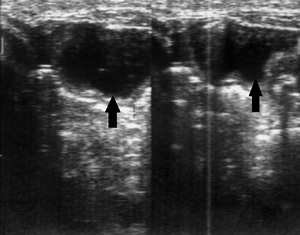

Ультразвуковыми признаками острой обтурационной тонкокишечной непроходимости являются:

• расширение просвета тонкой кишки более 2 см с наличием феномена "секвестрации жидкости" в просвет кишки;

• утолщение стенки тонкой кишки более 4 мм;

• наличие маятникообразной перистальтики;

• увеличение высоты керкринговых складок более 5 мм, увеличение расстояния между ними более 5 мм;

• гиперпневматизация кишечника в приводящем отделе;

• наличие свободной жидкости в брюшной полости.

КТ кишечная непроходимость

УЗ-признаки острой спаечной обтурационной тонкокишечной непроходимости.

Ширина просвета тонкой кишки достигает 32 мм, трехслойная структура стенки сохранена,

внутреннее содержимое практически

анэхогенное (стрелки).